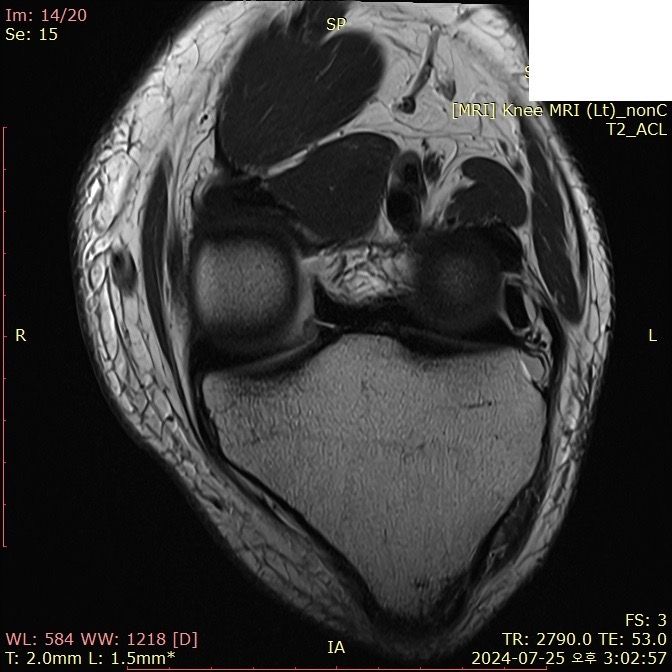

무릎 ACL(전방십자인대) 확인 부탁드려요

아스팔트에 무릎을 부딪쳐 심하게 부어서 mri 찍어봤는데 슬개골 비변위성 골절 판독 받은 건 기억 나는데, 인대는 기억이 잘 안나서 여쭤 봅니다..

전방십자인대 괜찮은가요...??ㅠㅠ

• 2번 째 사진